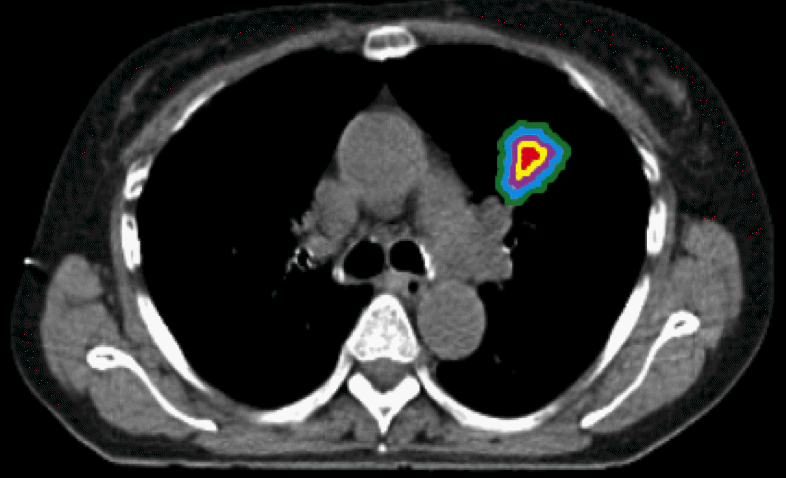

For both surgery and radiotherapy, clinicians need exact information about the extent of the tumor and of structures that must not be damaged. With a modern CT or MRI examination consisting of hundreds of images (obtained with different modalities or sequences), it is not realistic in clinical routine to do this manually. Thus, new automated methods for segmentation (delineation by identifying the boundary) are needed. In particular, when evaluating whether a tumor grows or shrinks during treatment, reliable segmentation methods are crucial. In this project, new segmentation techniques based on machine learning techniques, such as support vector machines, decision forests and deep learning (U-Net), are being developed and tested in available datasets of brain tumors, lung cancer and other types of tumors. The segmentation methods are compared to conventional manual segmentation, and agreement between automated and manual segmentation will be related to the variation between human observers. For future clinical applications, we correlate the findings with long-term clinical outcome.